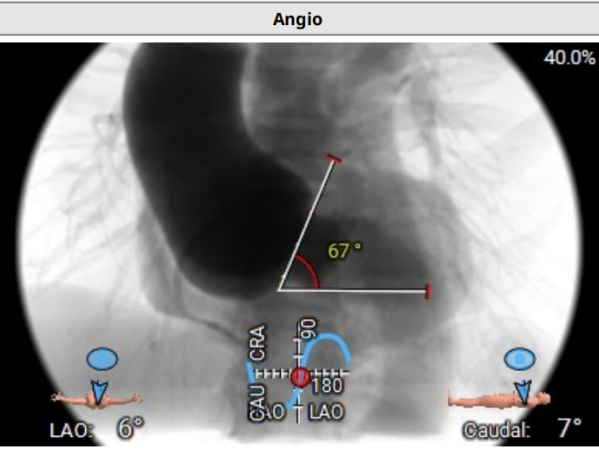

手术效果

成功植入Hanchor Valve(TAV29)瓣膜,术后无反流及瓣周漏。术前左室内压力为111/13 mmHg,主动脉压力为106/45 mmHg;术后左室内压力为90/7 mmHg,主动脉压力为89/48 mmHg。